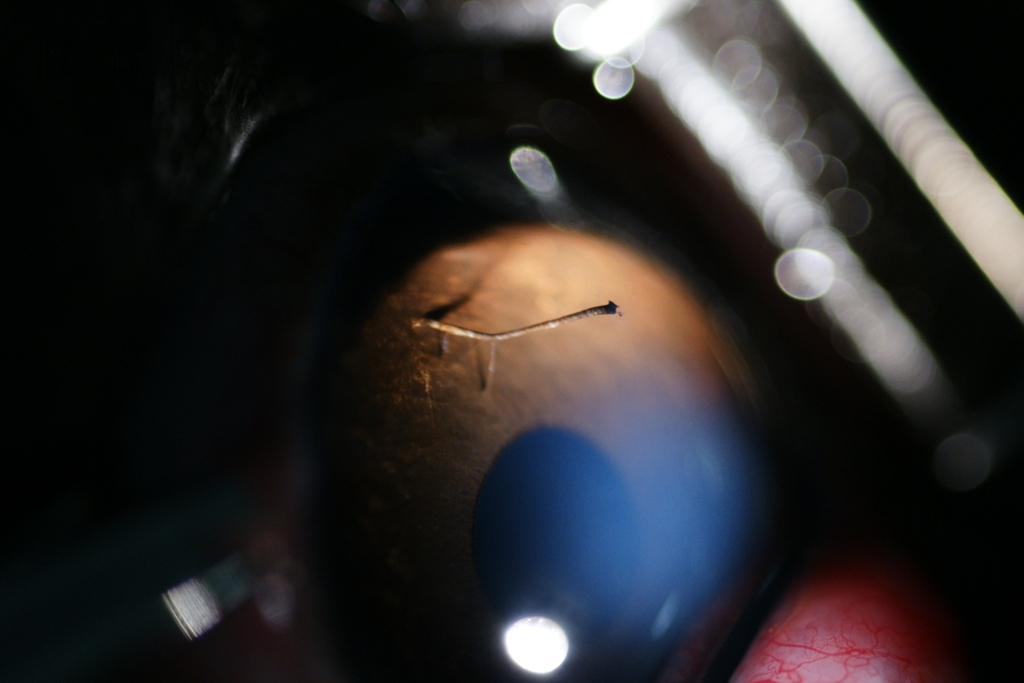

Persistance de membrane pupillaire chez un chaton (le truc bizarre à la droite du point lumineux). C'est complètement bénin

- 64530 (386.39 Kio) Consulté 2735 fois